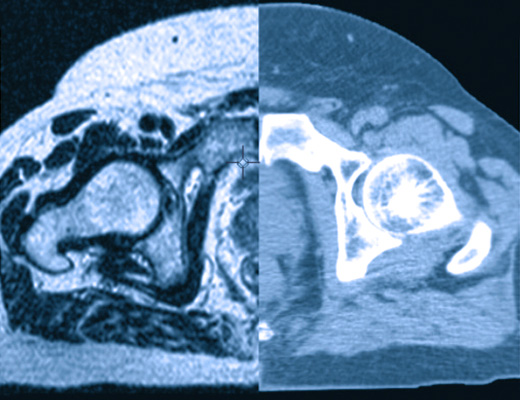

Para la planificacion este sistema permite la incorporacion de metodos complementarios de imagenes, siendo la base la Tomografia Axial. Estas imagenes pueden fusionarse con imagenes de Resonancia Magnetica y/o Tomografia por emision de positrones (PET), permitiendo al medico pasar de un conjunto a otro de imagenes de manera continua para seleccionar la mejor visualizacion tanto del blanco como de otras estructuras de interes.